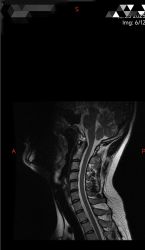

无标题 无名氏 2025-05-21(三)11:08:48 ID:hjxOZlq [举报] No.66125348 管理

po看我这个咋样啊( ´_ゝ`),是不是有点压到脊髓?

>>No.66125348

一点点吧不严重,有啥症状不

>>No.66125496

症状是几天重几天轻的,这核磁是症状轻的时候拍的。症状重的时候就是,胳膊有点沉,手指不灵活,说话时舌头有点打结。精神混混沉沉的,困,想睡觉

片子医生说没病,但我有症状( ´_ゝ`)

>>No.66126254

肥哥去推拿科看看( ゚ 3゚)

可能会多让你拍个颈椎正侧位片

通常这种就是颈椎不好搞得肩颈肌肉紧张影响血供( ゚ 3゚)

>>No.66126274

是西京,专门去看的(;´Д`)

有时候不舒服的时候,感觉脑子里面少了(个很重要的,应该是供血不足)东西一样,注意力记忆力下降,经常打哈欠流泪。洗完澡或者摆烂出去散心后症状轻一些( ´_ゝ`)。

我感觉那块颈椎骨像是松动了一样,一跑出正位就难受,一回到正位就没事(;´Д`)

其实高中后期脖子就有点不舒服,只是没注意也没啥问题。本科的时候严重,应该是急性期,当时真是脖子疼(现在不疼),感觉世界不真实,有时恶心,更厉害的打哈欠流泪胳膊沉(当时不舍得花钱去医院看,一是怕花钱,二是真怕查出点啥⊂彡☆))д´))。一直到读研现在比之前轻松点,但还是不舒服,于是打算去看了一下。。。

>>No.66126688

要不这样,好肥哥如果禁得起且愿意折腾,就先去神内或脑病挂个号,陈述病情,要求拍个头颅的MRI,看看人给不给开,要是还有余力去看看有心理疾病没有

一般来说颈椎病症状不会如此复杂(当然也有这种甚至更严重的),如果脑袋和心理都没问题的话那估计就纯是颈椎问题

肥哥你这个是核磁,比较难看出来骨排列,不愿意折腾就去推拿科之类的搞张颈椎正侧位+开口位X光片,看看能不能瞅出来啥问题